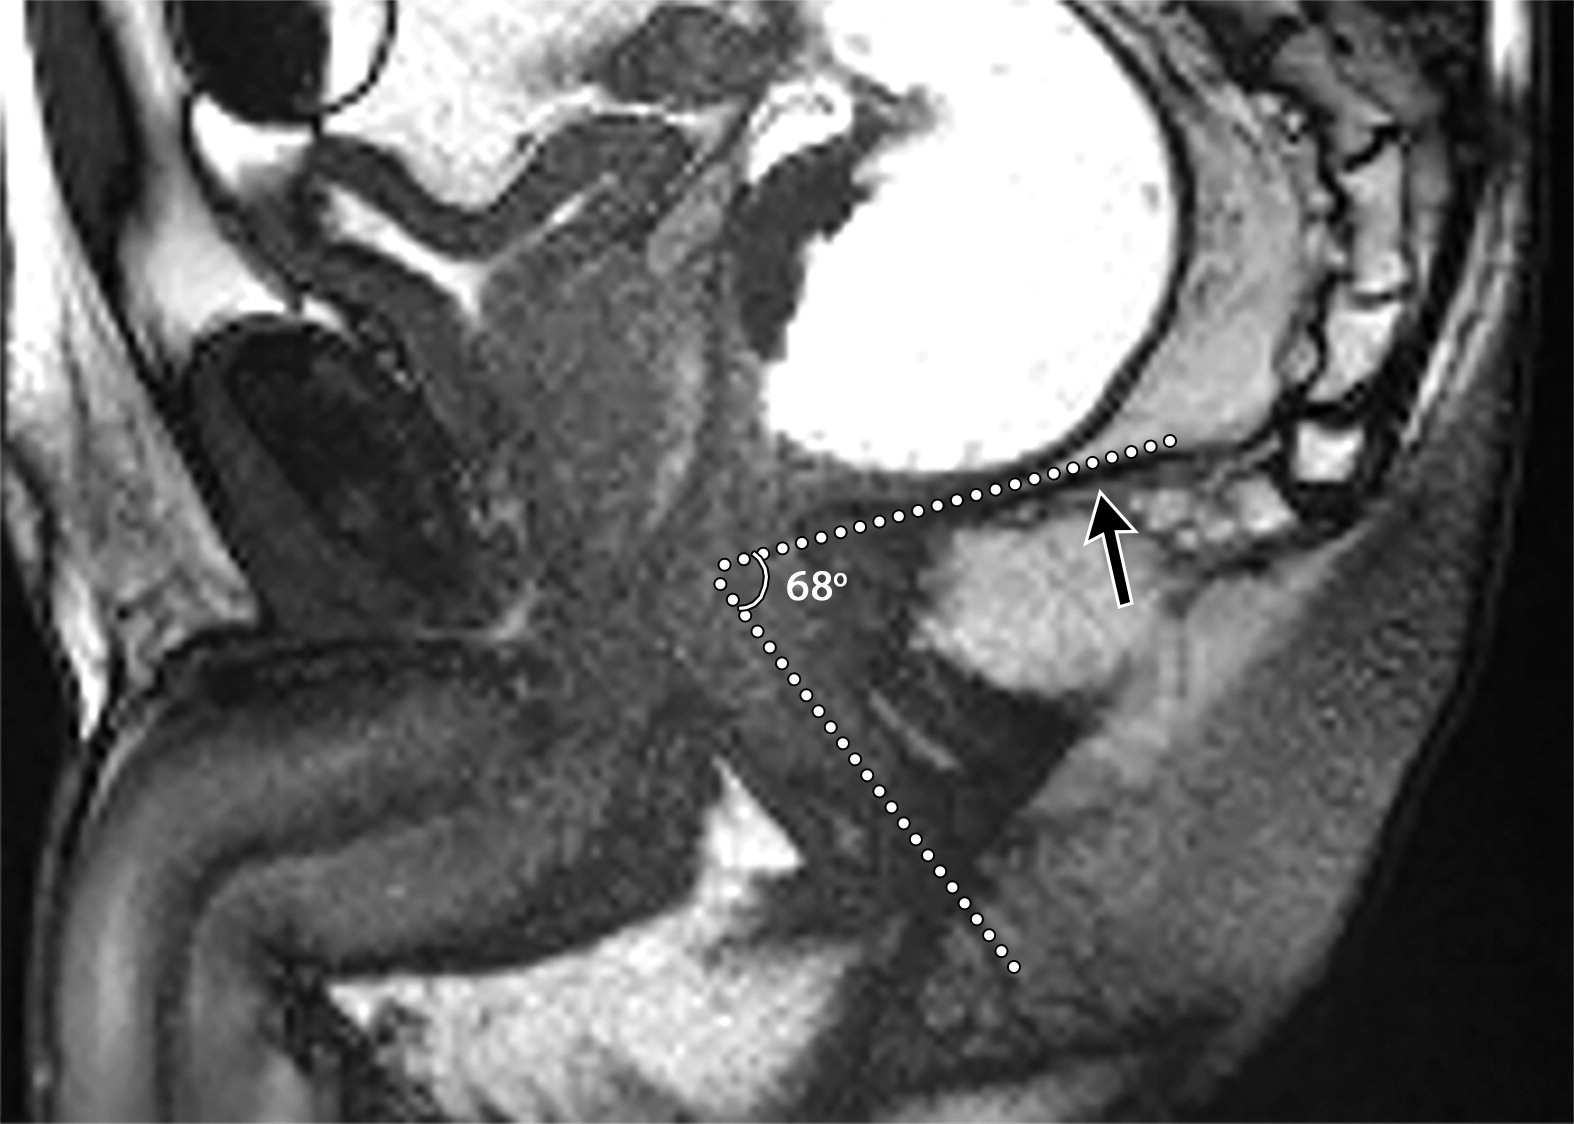

02b30ed4a7e2f5b218cd7c859419af04.jpegd7d20971f4726c22874ec1f489d536ad.jpeg6a942d5d2d6e82f6400de4b653353430.jpeg63岁男性的肛门直肠角。

(a)矢状位T2WI示肛门直肠角,即肛管中轴与远端直肠后壁之间的夹角为87°(白色点状虚线)。男性静息时正常角度约101°(图片未显示)。

(b)矢状位T2WI示提肛板(b图黑色长箭头)在增加腹压过程中正常抬高,导致肛门直肠角下降至68°。